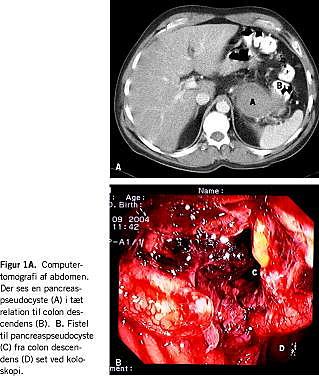

Fem dage efter indlæggelsen oplevede patienten et pludseligt ildebefindende med en stor opkastning samt diare med frisk blødning per rectum. Blodtrykket blev målt til 72/53 og pulsen til 126. Ved en efterfølgende computertomografi (CT) af abdomen sås der en udfyldning beliggende mellem pancreas, ventriklen og den venstresidige colon med målene 3,5 × 9 × 9 cm (Figur 1A ). Der udførtes koloskopi, hvor der ved venstre colonfleksur blev set tegn til blødning med perforationsåbning til en kavitet med koagler (Figur 1B). Mikroskopisvar fra colonbiopsier viste en overgangszone fra et område med colonslimhinde til et nekrotisk parti, der kunne repræsentere del af en fistel. Konklusionen var således en spontan ruptur af pancreaspseudocyste til colon descendens.